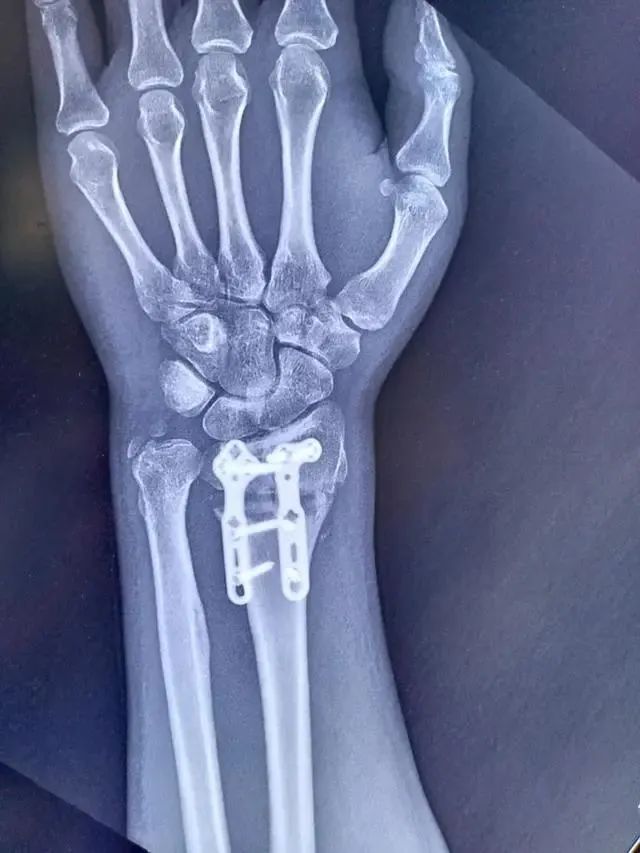

2022年9月,山大二院创伤骨科运用3D打印截骨导板,成功为一位被腕关节畸形困扰10年的患者进行手术。术后患者腕部功能得到极大改善,手指麻木消失,握力恢复到接近正常。

该患者10余年前桡骨远端骨折保守治疗导致腕关节畸形,出现腕关节活动受限、疼痛,伴有手指麻木、手部握力下降等症状,严重影响他日常劳动,于是来到山大二院创伤骨科治疗。

通过检查发现,患者的腕关节畸形包括桡骨高度、腕关节掌倾角及尺偏角的丢失,手术是治疗此类疾病的唯一方法。手术通过截骨纠正畸形,恢复患者腕关节的正常解剖。以往的手术畸形矫正程度依赖个人经验,存在畸形纠正不彻底,症状改善不满意等风险。

创伤骨科副主任医师霍延青团队经过术前评估,利用数字技术和医科交叉联合,为患者量身定制了手术导板,实施精准手术。术后,患者腕部功能得到极大改善,手指麻木消失,握力恢复到接近正常。

△术后正位片